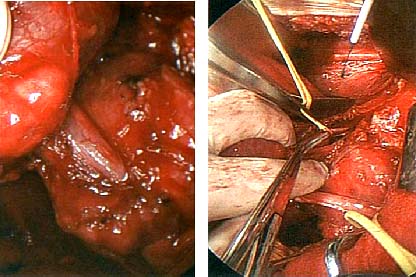

Không thể kết luận bản chất khối u là gì, chúng tôi đề nghị bệnh nhân nên chuyển vào Trung tâm chẩn đoán y khoa Hòa Hảo, thành phố Hồ Chí Minh để xác định thêm bằng siêu âm, CT và MRI cũng như sinh thiết bản chất nếu có thể. Kết quả tại TT chẩn đoán y khoa Hòa Hảo kêt luận là u dạng angiomyolipoma trên thận (P) và các cơ quan khác không có. Bệnh nhân đưa kết quả quay trở lại Viện Sốt rét KST-CT Quy Nhơn, sau đó bác sĩ ở đây liên hệ cho bệnh nhân sang một BV tại Singapore để can thiệp phẩu thuật và làm giải phẩu bệnh cũng cho ra là u angiomyolipoma, chẩn đoán phân biệt là u lao xơ hóa. Mổ cắt bỏ khối u kích thước 6.0 x 8.3cm, đang có dấu hiệu xuất huyết bên trong u do 3 điểm phình mạch nhỏ trên hệ mạch dọc theo dẫn đến u và kèm theo cắt toàn bộ thận vì khối u xâm lấn và nguy cơ suy thận đến gần. Không làm nút mạch vì u quá lớn.

Nút mạch có liên quan đến việc đưa một catheter vào trong mạch máu dẫn đến khối u, sau đó các mạch máu bị tắt, cụ thể là các nhà phẩu thuật sẽ tiêm ethanol hoặc các thành phần trơ. Quy trình làm có thể rất đau, vì vậy cần phải sử dụng thuốc giảm đau. Nhu mô thận bị phá hủy thường gây ra hội chứng sau nút mạch, biểu hiện buồn nôn, nôn mửa, sốt và đau bụng và kéo dài nhiều ngày. Nói chung, nút mạch có tỷ lệ khoảng 8% mắc bệnh và 2.5% tử vong. Các bệnh nhân bị mất thận nên được giám sát và theo dõi cẩn thận huyết áp, nếu có cao huyết áp thì cần điều trị và tránh các loại thuốc có khả năng gây độc cho thận như một vài thuốc giảm đau chất cản quang. Các bệnh nhân như thế không thể truyền thông một cách hiệu quả (do tuổi tác hoặc do khuyết tật về trí não) lúc mất nước. Nếu nhiều khối u AML hoặc khối u lớn có thể dẫn đến bệnh lý thận mạn tính, cần thẩm phân phúc mạc hay các liệu pháp thay thế thận khác.